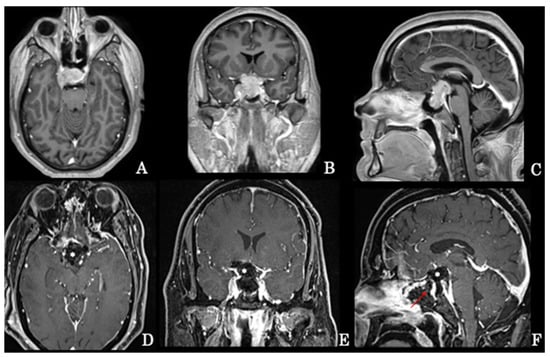

Figure 1. Preoperative axial (A), coronal (B), and sagittal (C) MRI scans of a giant intra-suprasellar pituitary adenoma also extending into the right cavernous sinus that has undergone extended endoscopic removal. Early postoperative axial (D), coronal (E), and sagittal (F) MRI scans revealing the gross total resection of the tumor; the surgical cavity has been filled with autologous fat (*) and the osteodural breach covered with a pedicled nasoseptal flap (arrow) according to the 3F technique.

A vascularized nasoseptal flap, collected during the procedure, can be used for final reconstruction [16]. Recently, our school defined the “3F technique” [18] as follows: it consists of the use of a fat autologous periumbilical graft fixed with fibrin glue across the intra-extradural as a cork and then covered with a nasoseptal “fresh flap”; the patient is mobilized very early to divert the intracranial pressure and pulsation of the defect (Figure 1D–F).